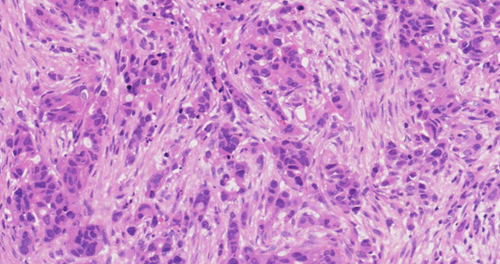

强子漫读系列-01-20-041-肝细胞癌-肉瘤样梭形细胞亚型(二)

2023年02月10日 1413 08分29秒